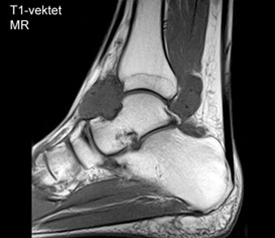

Røntgenbillede vil som regel give diagnosen, idet det viser mange forkalkede mus inde i leddet. Der kan også være slidforandringer. Tidligt i sygdommens forløb kan der dog mangle forkalkninger. MR-skanning er den bedste undersøgelse og kan være nødvendig ved manglende fund ved røntgen eller før en eventuel operation.